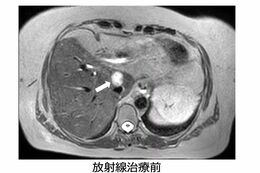

エレクタユニティは、照射プランを装置に送るところまでは同じ。画期的なのは患者さんが治療台に寝て、準備が整ったところで、MRIを使って撮影し、高精度の画像を見ながら照射プランを調整し、照射中もMRIをとって位置を調整できるのだ。

この方法で治療を行うと正確にがんだけを狙いやすくなるので、ほかの臓器を傷めにくいのだ。

エレクタユニティはその場でターゲットを絞って照射できるため、周辺を傷つけず、大幅に後遺症が軽減されるのだ。

「従来は、膵臓、肝臓など消化器に近いところのがんは、線量を抑えて照射をしていましたが、エレクタユニティならほかのがんと同様の線量を照射することができます。転移がないステージ1~2のがんなら、ほとんど治療が可能です」